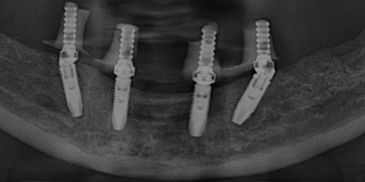

The All-on-4 and All-on-6 concepts are immediate-function protocols for the rehabilitation of the completely edentulous (toothless) jaw. These procedures allow for the placement of a full-arch fixed prosthesis on four or six dental implants, often avoiding the need for extensive bone grafting.

The All-on-4® and All-on-6 concepts are advanced surgical and prosthodontic protocols designed for the immediate rehabilitation of patients with completely edentulous jaws or those with failing dentition.

The surgical phase focuses on preparing the jawbone and placing the implants to ensure sufficient primary stability for immediate loading.

Implant Placement and Angulation:

Two implants are placed vertically in the front (anterior) region of the jaw where bone density is typically highest.

Posterior Implants (The "Tilted" Technique): In the All-on-4 protocol, the two back (posterior) implants are placed at an angle of up to 45 degrees.

Why tilt the implants? This angulation allows the surgeon to anchor the implants in better quality anterior bone while avoiding anatomical structures like the maxillary sinus (in the upper jaw) or the mandibular nerve (in the lower jaw). It also increases the contact area between bone and implant.

If bone conditions allow, tilted implants are avoided. Instead, two additional implants are placed in the posterior (back) region, bringing the total to six implants (All-on-6) instead of four.

Multi-Unit Abutments: Once the implants are placed, angled abutments (Multi-Unit Abutments) are screwed onto the implants. These correct the angle of the tilted implants, making them parallel so the prosthesis can sit flat and passive.